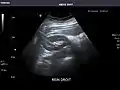

Aorta: Visualized portions normal in caliber, 16 x 15 mm.

Aorta